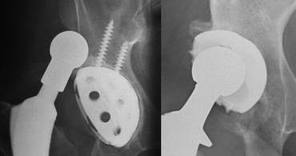

Implants for revision hip surgery

The implants used for the revision operation are broadly similiar to the ones used for first time sugery. They consist of a cup section inserted into the natural socket of the pelvis and a stem with a ball at its top aspect that is inserted into the femur bone. When the two are put together, a joint results much as is the case in nature where the ball at the top end of the thigh bone forms a joint with the hollow socket of the pelvis bone.

In many instances however, the implants required for revision surgery are more complicated and have to be selected for each individual patient depending upon the prevailing clinical situation.

The socket component increasingly used for revision surgery nowadays is of the type that is implanted without cement. It has to be said however, that some surgeons do continue to report good results from revisions carried out with cemented socket components. The implants used without cement are of a range of sizes and the most appropriate one for a particular patient can be chosen at the time of surgery and inserted after a trial fit. On occasion, even the largest sized component may not be satisfactory and this is particularly the case when the bone loss is significant and also where it has occured only in one sector of the natural socket as opposed to uniformly all round the socket. In such situations, the surgeon may used specialised components that have “add ons” to allow better filling of any defects. These “add on” modules are assembled to the artificial socket prior to implantation into the patient.

There are instances when the bone defects are so great that there is insufficient bone to anchor satisfactorily, a socket without using cement. In such a situation, the surgeon has the option of using socket reinforcing steel cages that are first implanted into the damaged socket much like a scaffold for a building. A socket can then be cemented within the scaffold. If the bone loss is even greater, say in a situation when damage from the failed replacement has caused a large hole in the natural socket of the pelvis, a large shield with an integral metal shell is first placed on the bone. This is held by means of screws placed via the shield into relatively intact bone. The shield achieves stability by overlapping the margins of the socket. Once this has been fixed in place, the plastic socket may be cemented into it’s cavity. Larger and more complex metal components and replacement parts are available to deal with bigger bone losses.

Uncemented sockets: A technique that has gained increasing popularity in the last 7-10 years is the use of metal components without cement for revision of the acetabulum. These shells are very much like those used in primary surgery but have addtional holes provided so as to allow maximum flexibility to the surgeon is inserting supplemental screws. This is particularly useful where the bone is weak and the interference fit of the metal socket and bone, relatively poor.

More recently, these implants are being coated with hydroxyappatite which appears to promote the growth of bone onto the special surface of the metal shell. In some of the more complex cases with assymetric or unusal patterns of bone loss, the shells are available with modular “add ons” of different sizes that can be fixed to the shell to match the individual patient’s bone deficiency. This means that the surgeon is not limited to simply implanting larger and larger hemispherical metal shells to make up a deficiency that exists only in one sector of the socket.